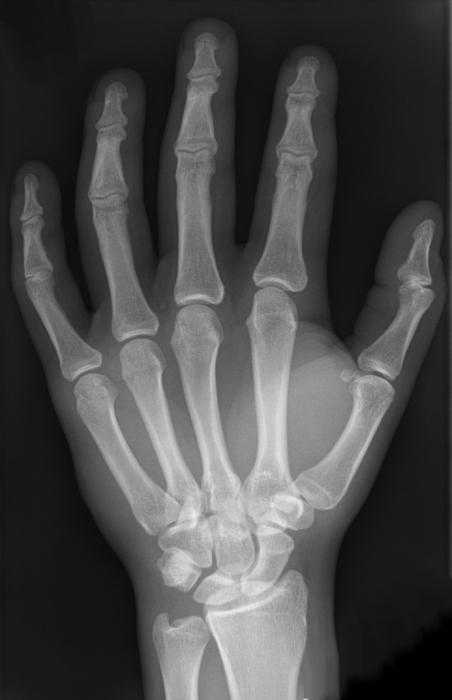

Так как руки должны выполнять довольно точные и затейливые движения, строение костей кисти руки также чрезвычайно сложное. В запястье – 8 маленьких костей неправильной формы, расположенных в два ряда. На рисунке ниже можно увидеть строение кисти правой руки.

Проксимальный ряд образует суставную поверхность, выпуклую к лучевой кости. В него входят кости, если считать от пятого к большому пальцу: гороховидная, трехгранная, полулунная и ладьевидная. Следующий ряд – дистальный. Он соединяется с проксимальным суставом неправильной формы. Дистальный ряд состоит из четырех костей: трапециевидной, многоугольной, головчатой и крючковидной.

Кости пясти

Этот отдел, состоящий из 5 трубчатых пястных костей, также демонстрирует затейливое строение кисти руки. Скелет этих трубчатых костей сложен. Каждая из них имеет тело, основание и головку. Пястная кость 1-го пальца короче других и отличается массивностью. Вторая пястная кость – наиболее длинная. Остальные уменьшаются в длине по мере удаления от первой и приближения к локтевому краю. Основания вышеупомянутых костей пясти сочленяются с костями, образующими запястье. Первая и пятая пястные кости имеют основания с суставными поверхностями седловидной формы, другие – плоские. Головки пястных костей, имеющие суставную поверхность (полушаровидную), сочленяются с проксимальными пальцевыми фалангами.

Кости пальцев

У каждого пальца, за исключением первого, который состоит только из двух фаланг и не имеет средней, есть 3 фаланги: дистальная, проксимальная и средняя (промежуточная). Наиболее короткие – дистальные; проксимальные – наиболее длинные. На дистальном конце имеется головка фаланги, а на проксимальном – ее основание.